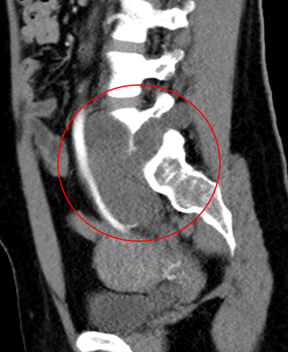

患者50岁女性,因体检发现右锁骨肿物10余天来诊。入院后X光片示右锁骨胸骨端膨大,密度减低,CT及MRI检查提示右侧锁骨局部骨性凸起伴周围肿块形成,考虑右锁骨胸骨端软骨肉瘤。

图片 1.png